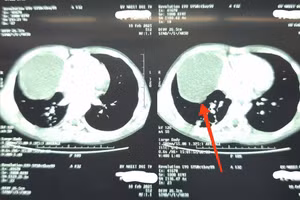

GD&TĐ - Sau cú ngã, trẻ cảm thấy đau vùng sườn phải và khó thở. Các bác sĩ chẩn đoán, trẻ có khối u nang bì trong lồng ngực.